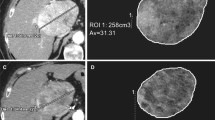

For all measurements, a semi-automated quantification software (Philips IntelliSpace Portal) was used (Fig. 2). Accuracy and reproducibility were previously demonstrated [7, 8, 13, 17,18,19]. Two readers with 6 and 7 years of experience supervised the measurements. A signal intensity greater two standard deviations than the average signal intensity measured within a region of interest (ROI) of 10 × 10 × 10 mm in the musculus erector spinae was defined an arterial vascularization. As most patients had multifocal disease with more than 3 lesions in 97% of the cases, a maximum of three dominant lesions were analyzed and combined as surrogate total tumor volume (TTV) and enhancing tumor volume (ETV). In each case, the same lesions were measured before and after treatment. The measurements are given in milliliters. Relative vascularization was calculated as the ratio of ETV and TTV and expressed as percentage.

Quantification of total tumor volume and enhancing tumor volume on baseline and follow-up imaging. a Patient with highly vascularized HCC. Images only show representative tumor measurements in one layer. Target lesions were volumetrically assessed. A Preinterventional MRI: tumor tissue appears highly vascularized compared to surrounding liver parenchyma. B Colored enhancing tumor volume/total tumor volume (ETV/TTV) overlay. C Postinterventional MRI: the tumor appears to be de-vascularized after treatment. D ETV/TTV overlay. b Patient with intermediately vascularized HCC. A Preinterventional MRI: Intermediate vascularization of tumor; relative arterial vascularization is color-coded in (B). C Postinterventional MRI: a tumor with initially intermediate vascularization loses hyper-vascularization compared to surrounding liver tissue. D ETV/TTV overlay